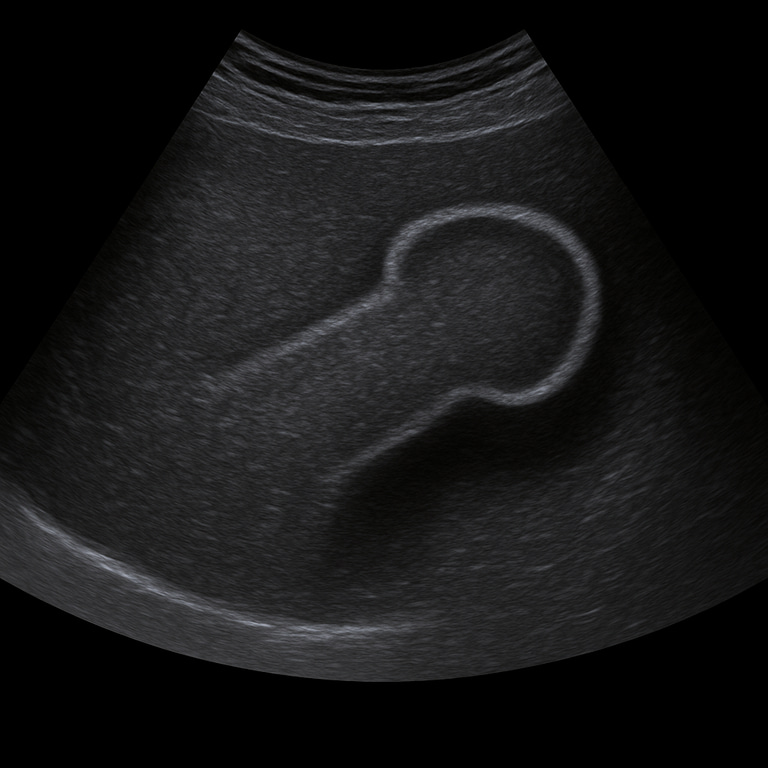

A penile ultrasound is used to examine tissue, blood flow and any structural changes in the shaft of the penis. The examination is performed by a specialist in radiology and provides real-time images that can show vascular changes, scarring, calcifications or signs of damage. Penile ultrasound is often used in cases of pain, swelling, curvature or suspected vascular involvement.

Unlike MRI or CT, which are used for more extensive tissue damage or tumor investigation, ultrasound is a fast, radiation-free and effective method for assessing vascular flow and soft tissues in the penile shaft. Using Doppler technology, the doctor can analyze blood flow in the corpora cavernosa in real time.